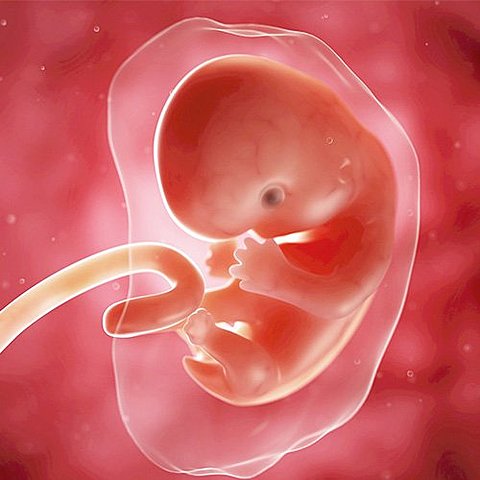

En la quinta semana de embarazo, el embrión mide entre 1 y 2 milímetros. Durante estas primeras y cruciales semanas, sus órganos vitales, huesos y sistema nervioso inician su desarrollo. El embrión se ha dividido en tres capas, que darán lugar a los futuros órganos del bebé: el ectodermo, el endodermo, y el mesodermo.

• Sexta y séptima semana

Sexta y séptima semana

Progresa el desarrollo de la traquea, la laringe y bronquios. La cavidad oral y nasal comienzan a separarse, se forma el paladar. Se encontraron más las piernas y los brazos que parecen aletas. Es la osificación de los miembros inferiores.

• Octava semana

Octava semana

En la semana 8 de embarazo, el embrión mide 8-11 milímetros, aproximadamente. En la semana 8 de embarazo, los ojos y orejas del embrión empiezan a crecer, los dedos de sus pies y manos comienzan a formarse, aunque aún permanecen unidos, y los codos ya son visibles.